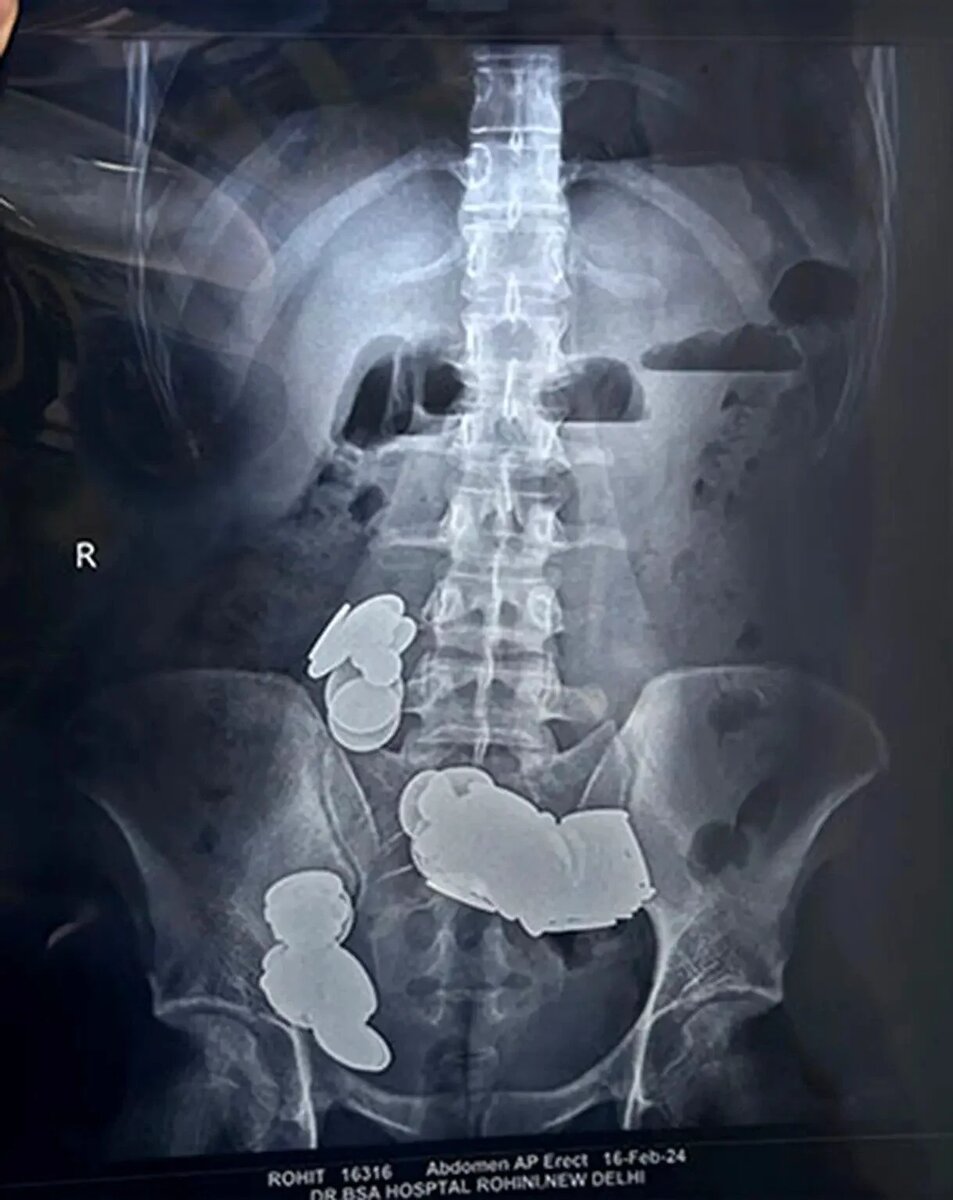

Снимок из интернета, максимально близкий к снимку пациента

На снимке — в кишечнике стопки монет по всей протяжённости, разного размера. Он глотал даже пятирублёвые. Насчитали около 50 штук: местами они шли красивыми столбиками, местами — поодиночке. Были ещё какие-то маленькие железяки — как потом оказалось, такие металлические скобки, которые на упаковке колбасы по краям. Жалко, фотография снимка пропала вместе со старым телефоном.